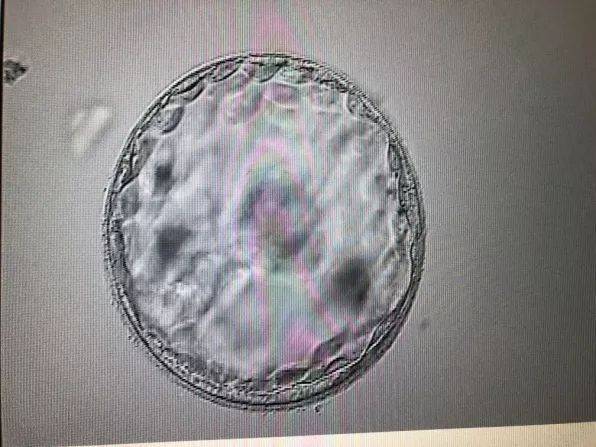

卵巢过度刺激综合征(OHSS):这是取卵手术后可能出现的并发症,由于促排卵药物的使用,卵巢会变得肿大,并分泌过多的液体到腹腔,导致腹胀、腹痛等症状。轻度OHSS通常会在几天内自行消退,而严重的OHSS则需要及时就医。